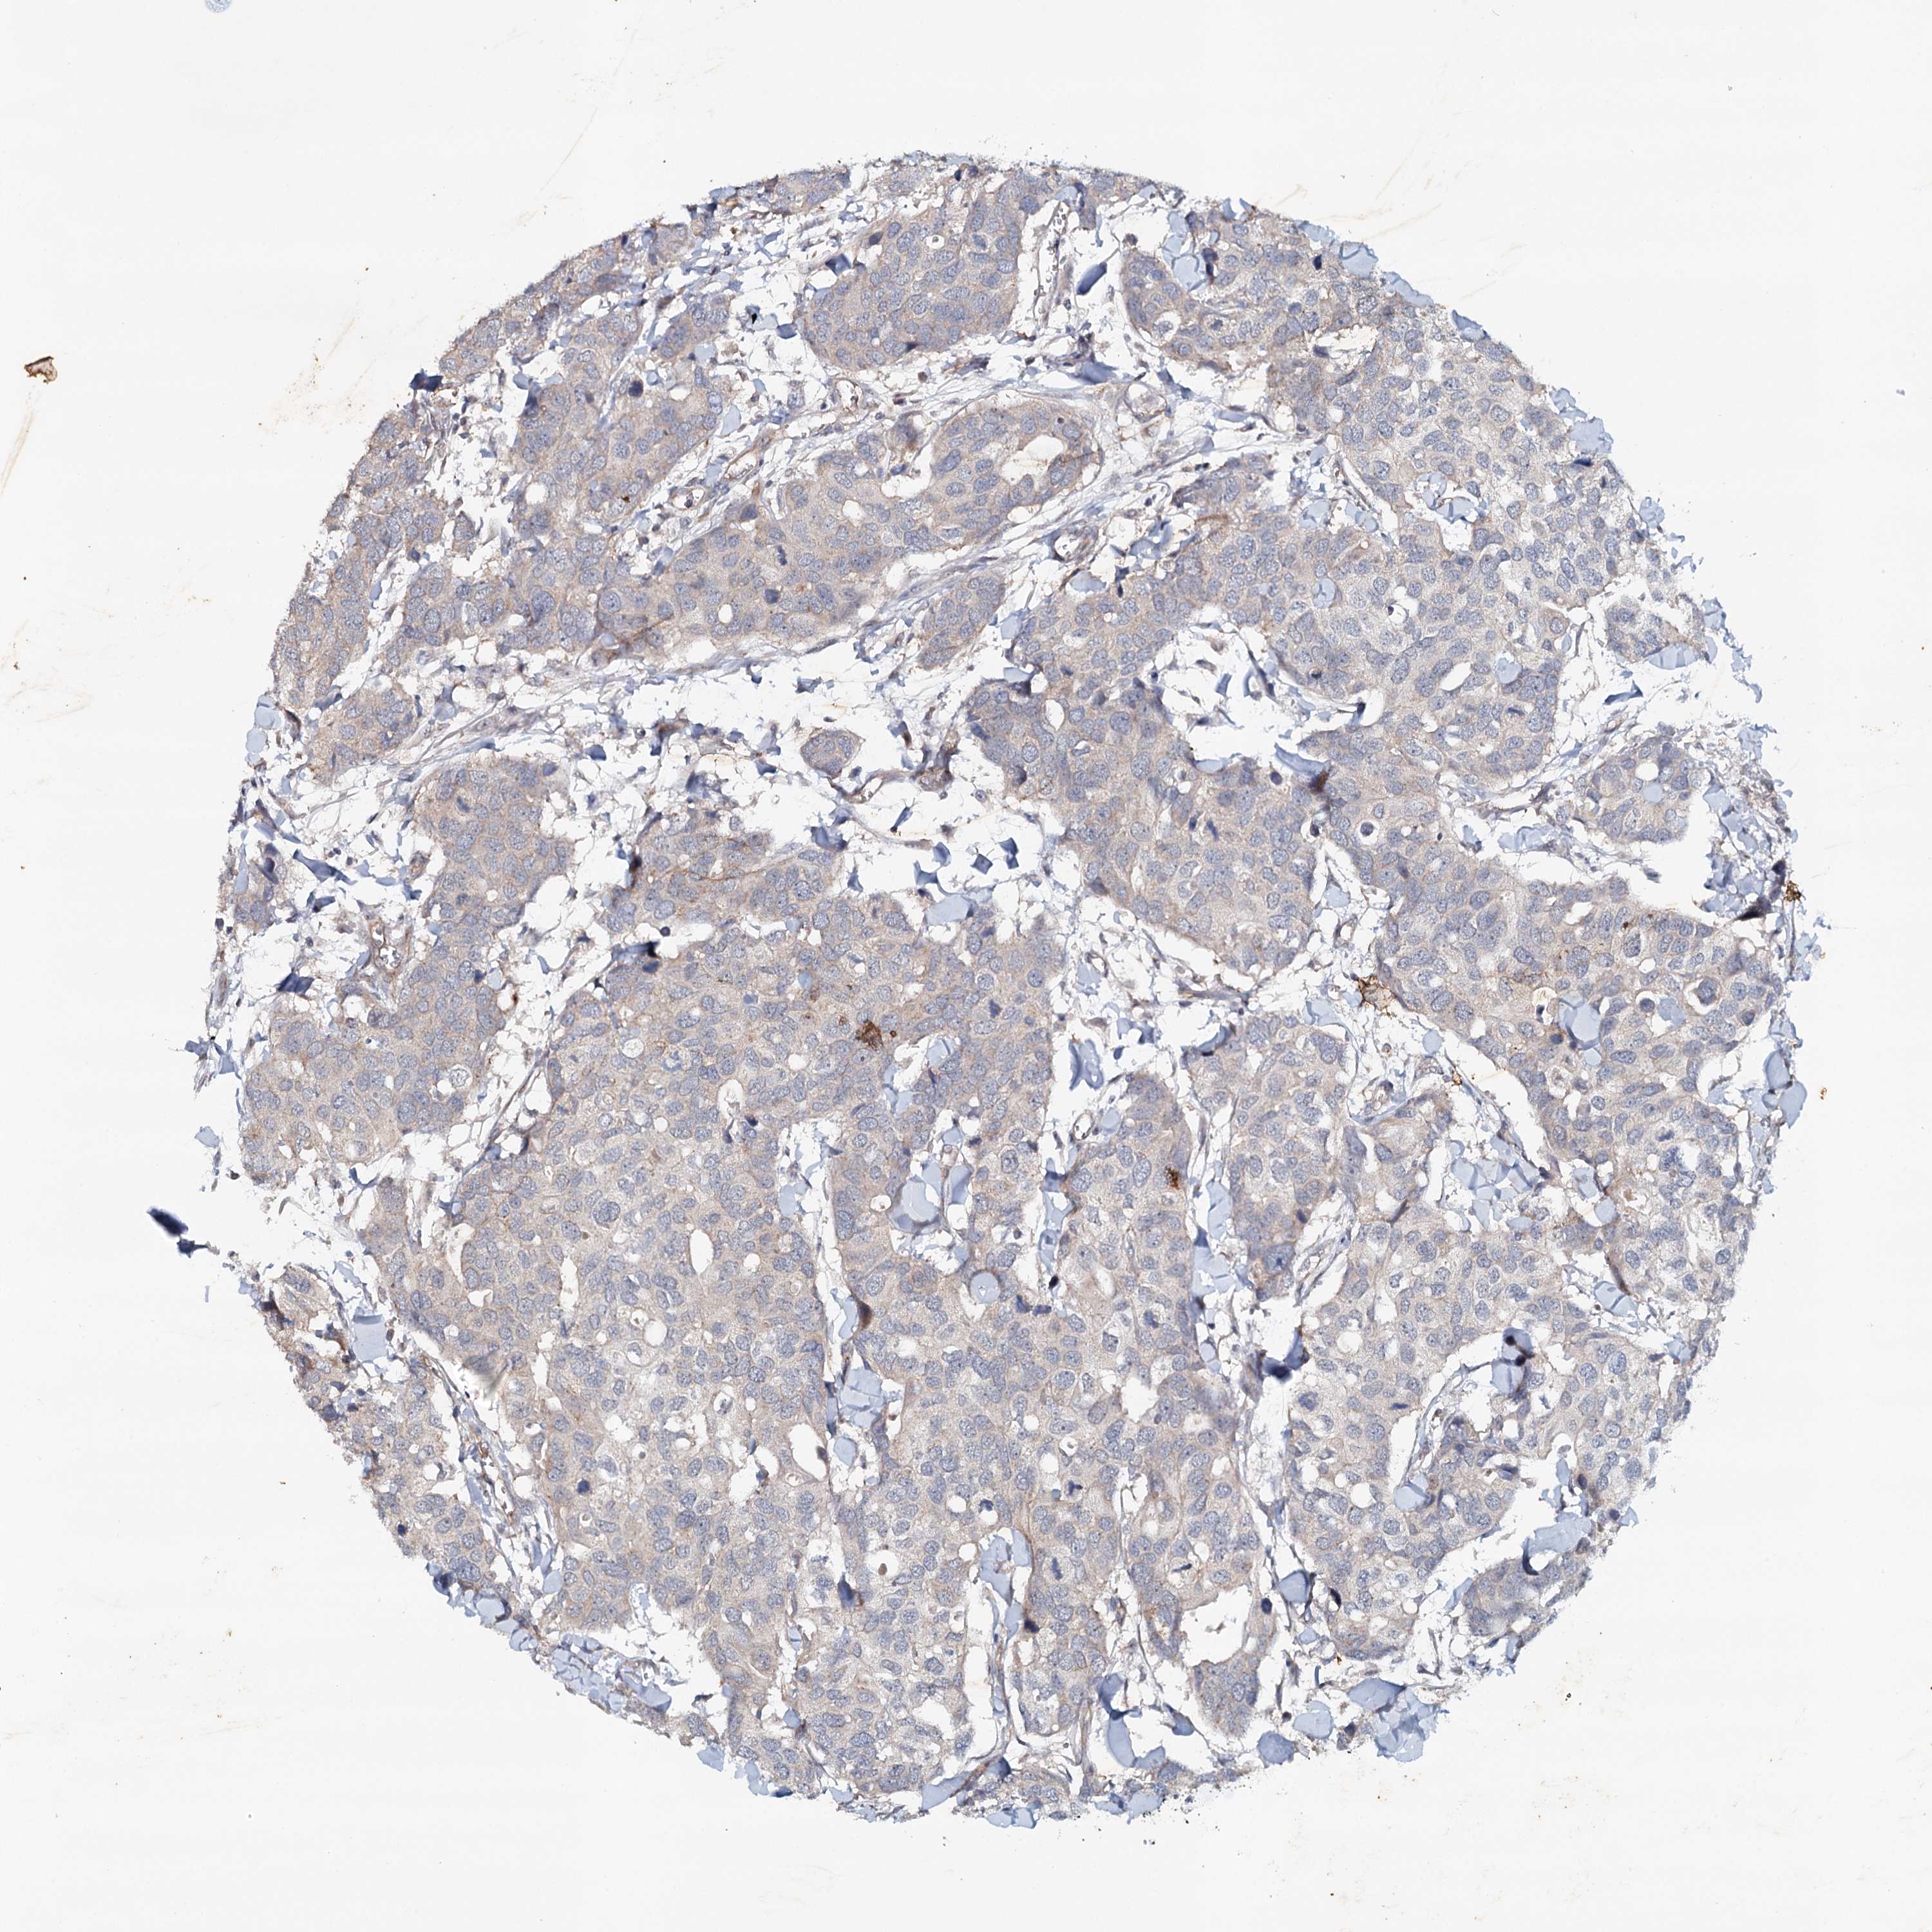

CANCER BREAST CANCER Show tissue menu

BRCA TCGA BRCA VALIDATION PROTEIN EXPRESSION

ANTIBODIES

AND

VALIDATION